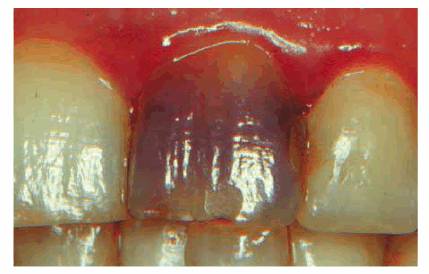

detecting color shifts in a crown (Figures 19-1A, and 19-1B). A tooth with a pink or reddish

hue would more than likely indicate internal hemorrhage from a recent injury (Figure 19-2), a dental procedure (Figure 19-3), or gingival tissue hyperplasia

Figure 19-1A: Transillumination of a maxillary left central incisor with a necrotic pulp.

Figure 19-1B: Transillumination of the adjacent tooth with a vital pulp. Because there is active blood flow through the live pulp tissue, the tooth appears brighter to the fiber-optic light than the adjacent tooth with a necrotic pulp.